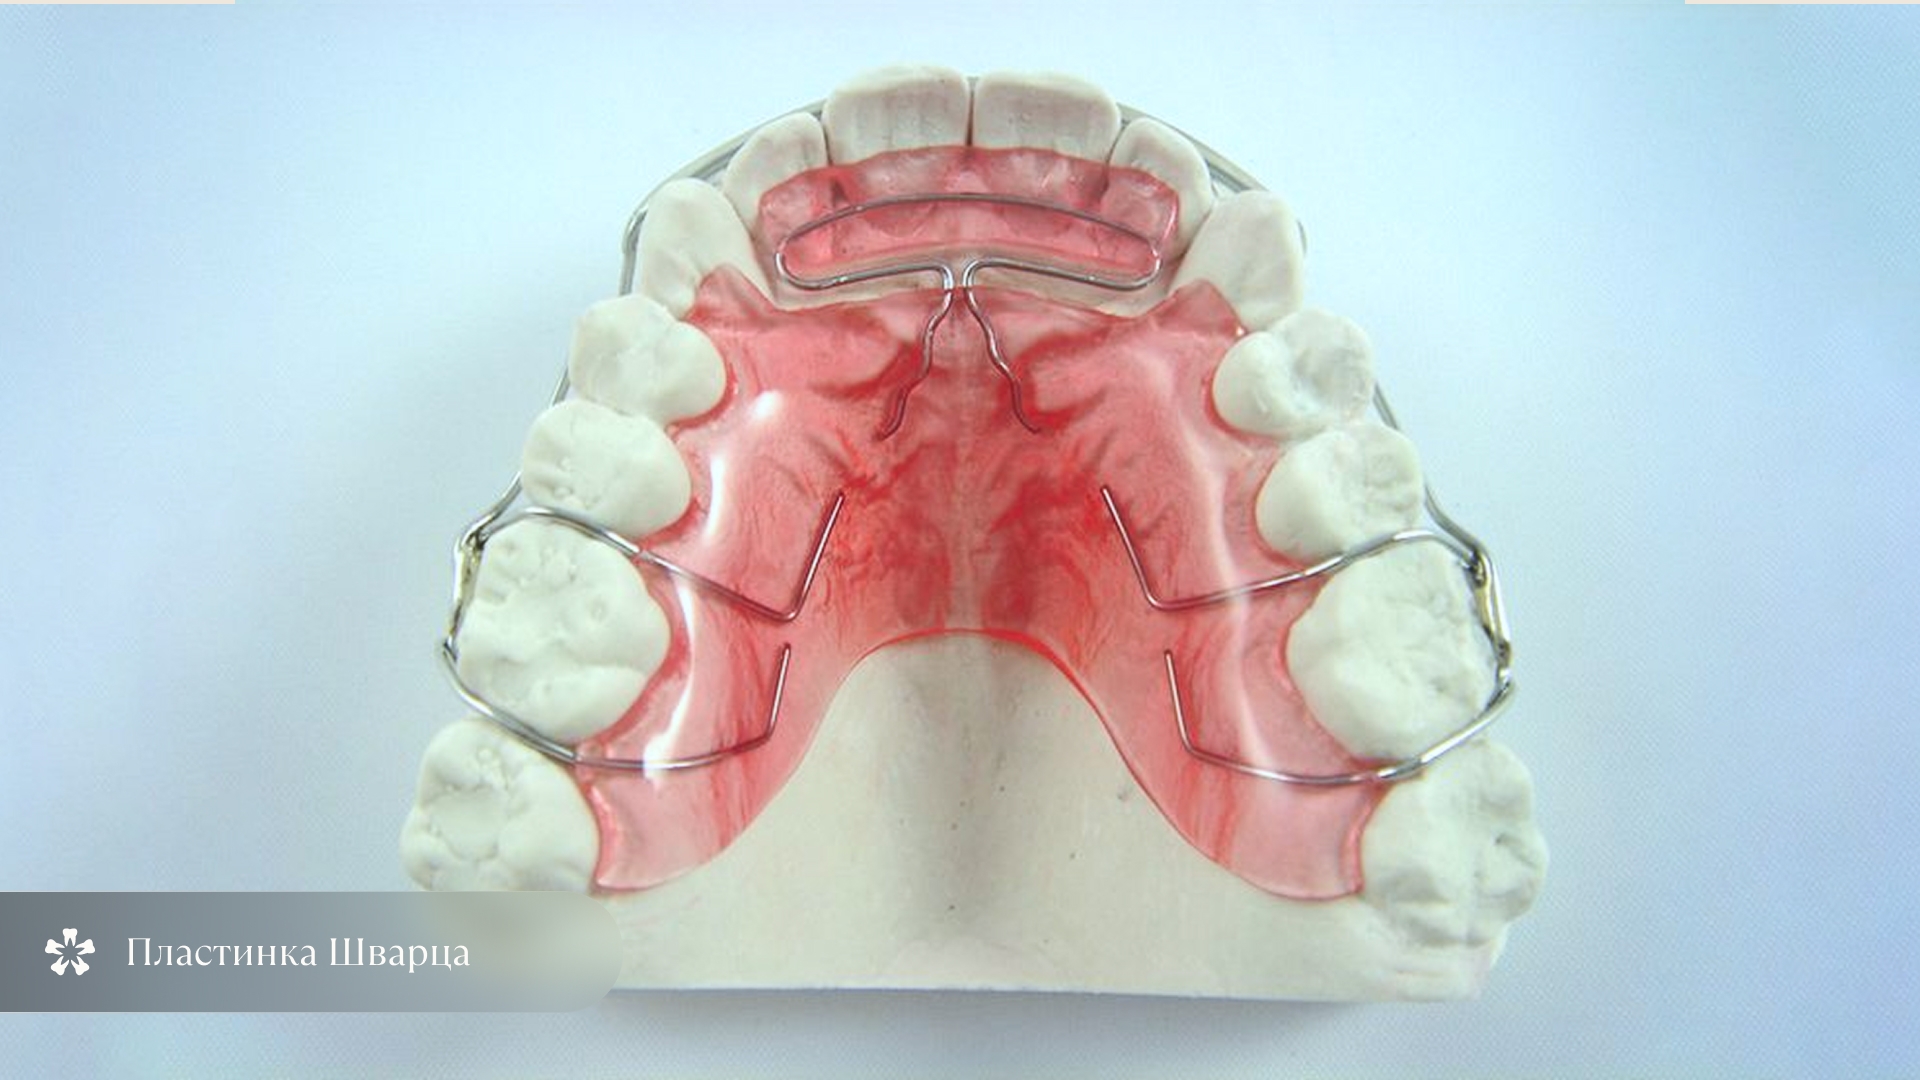

Пластиночные съёмные аппараты

Механизм: съемные аппараты, которые воздействуют на отдельные зубы или участки челюсти с помощью пружин, винтов, дуг. Могут сдерживать рост одной зоны и стимулировать рост другой.

Возраст: от 6 до 12 лет — в период сменного прикуса.

Плюсы: изготавливаются индивидуально по показаниям,, могут корректируют не только положение зубов, но и ширину челюстей.

Минусы: требуют постоянного ношения (16–20 часов в сутки), нуждаются в регулярной коррекции у врача.

Стоимость: от 20 до 40 тысяч рублей за один аппарат.

Сроки лечения: от 6 месяцев до 2 лет, чаще всего в сочетании с другими методами.